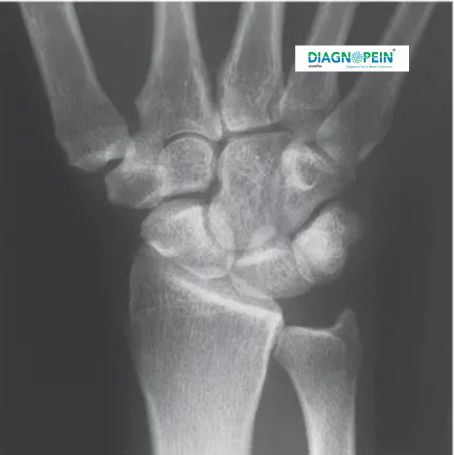

CT Right Wrist scan is an advanced imaging test that uses specialized X-ray technology to produce detailed cross-sectional images of the bones, joints, and soft tissues in the right wrist. It helps doctors detect fractures, ligament injuries, joint abnormalities, and bone disorders with high precision. At Diagnopein Nashik, the CT wrist scan is performed by trained radiology experts using multi-slice scanners that ensure quick and painless imaging.

Unlike traditional X-rays, the CT wrist scan captures minute details of bone structures, cartilage, and surrounding tissues. This makes it an essential diagnostic tool for orthopedic specialists, sports medicine practitioners, and surgeons to evaluate and plan accurate treatment.